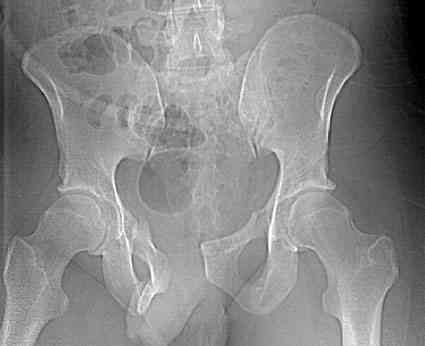

18.12. - отдельное спасибо еще раз А.В.Рункову- больного оперировали (А.В.Рунков) - произведен остеосинтез аппаратом - фиксация за крылья, два стержня в лонные кости и репозиция (почти полная) снимки будут чуть позже.

Дренировали отслойки на бедрах с их санацией. В правой ягодичной области сформировалась зона некроза. Больной "подвешен" за аппарат.